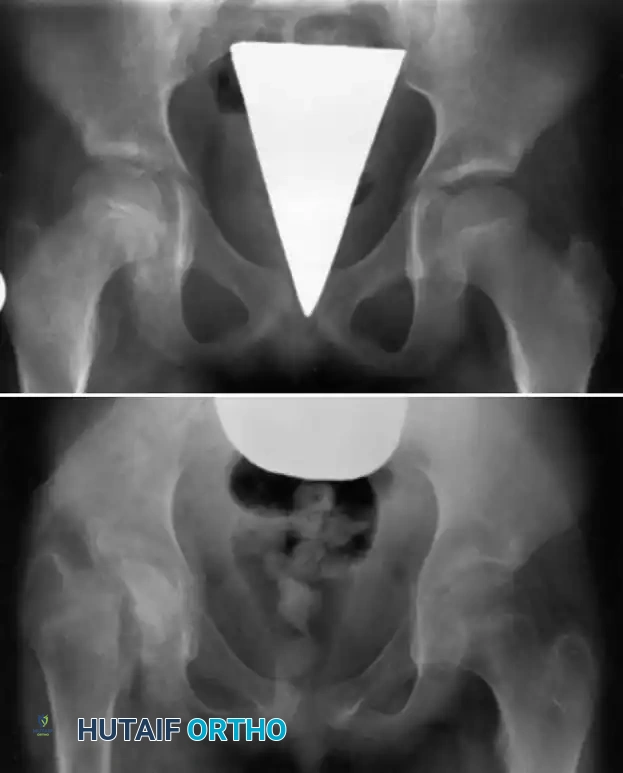

Fig. 16-3 Epiphyseal separation caused by infection in a young child. Note the catastrophic joint involvement secondary to transphyseal spread.